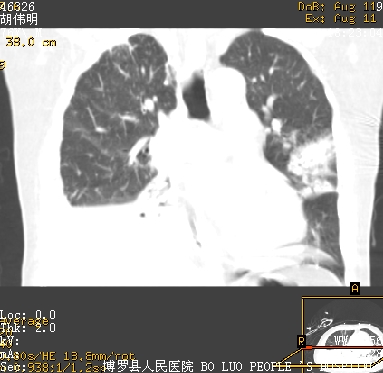

icu病人,几天都没明确诊断。m,76y,咳嗽、咳痰1周,伴气促,右胸痛入院,pe:t38.3c p135 r25 bp135/85。双肺可闻及大量湿罗音,心、腹未见明显异常。诊断:1心衰?2肺部感染?3冠心病?

11号ct

双肺感染性病变,下叶膨胀不全,胸水,左室大。

1)两肺感染性病变(右肺下叶肺脓肿可能)。2)双侧胸腔积液,以右侧为甚。

ards,肺感染性病变,右下叶实变,双侧胸腔积液,右侧为著,叶间胸膜积液,右上肺陈旧性tb纤维灶,左室大。